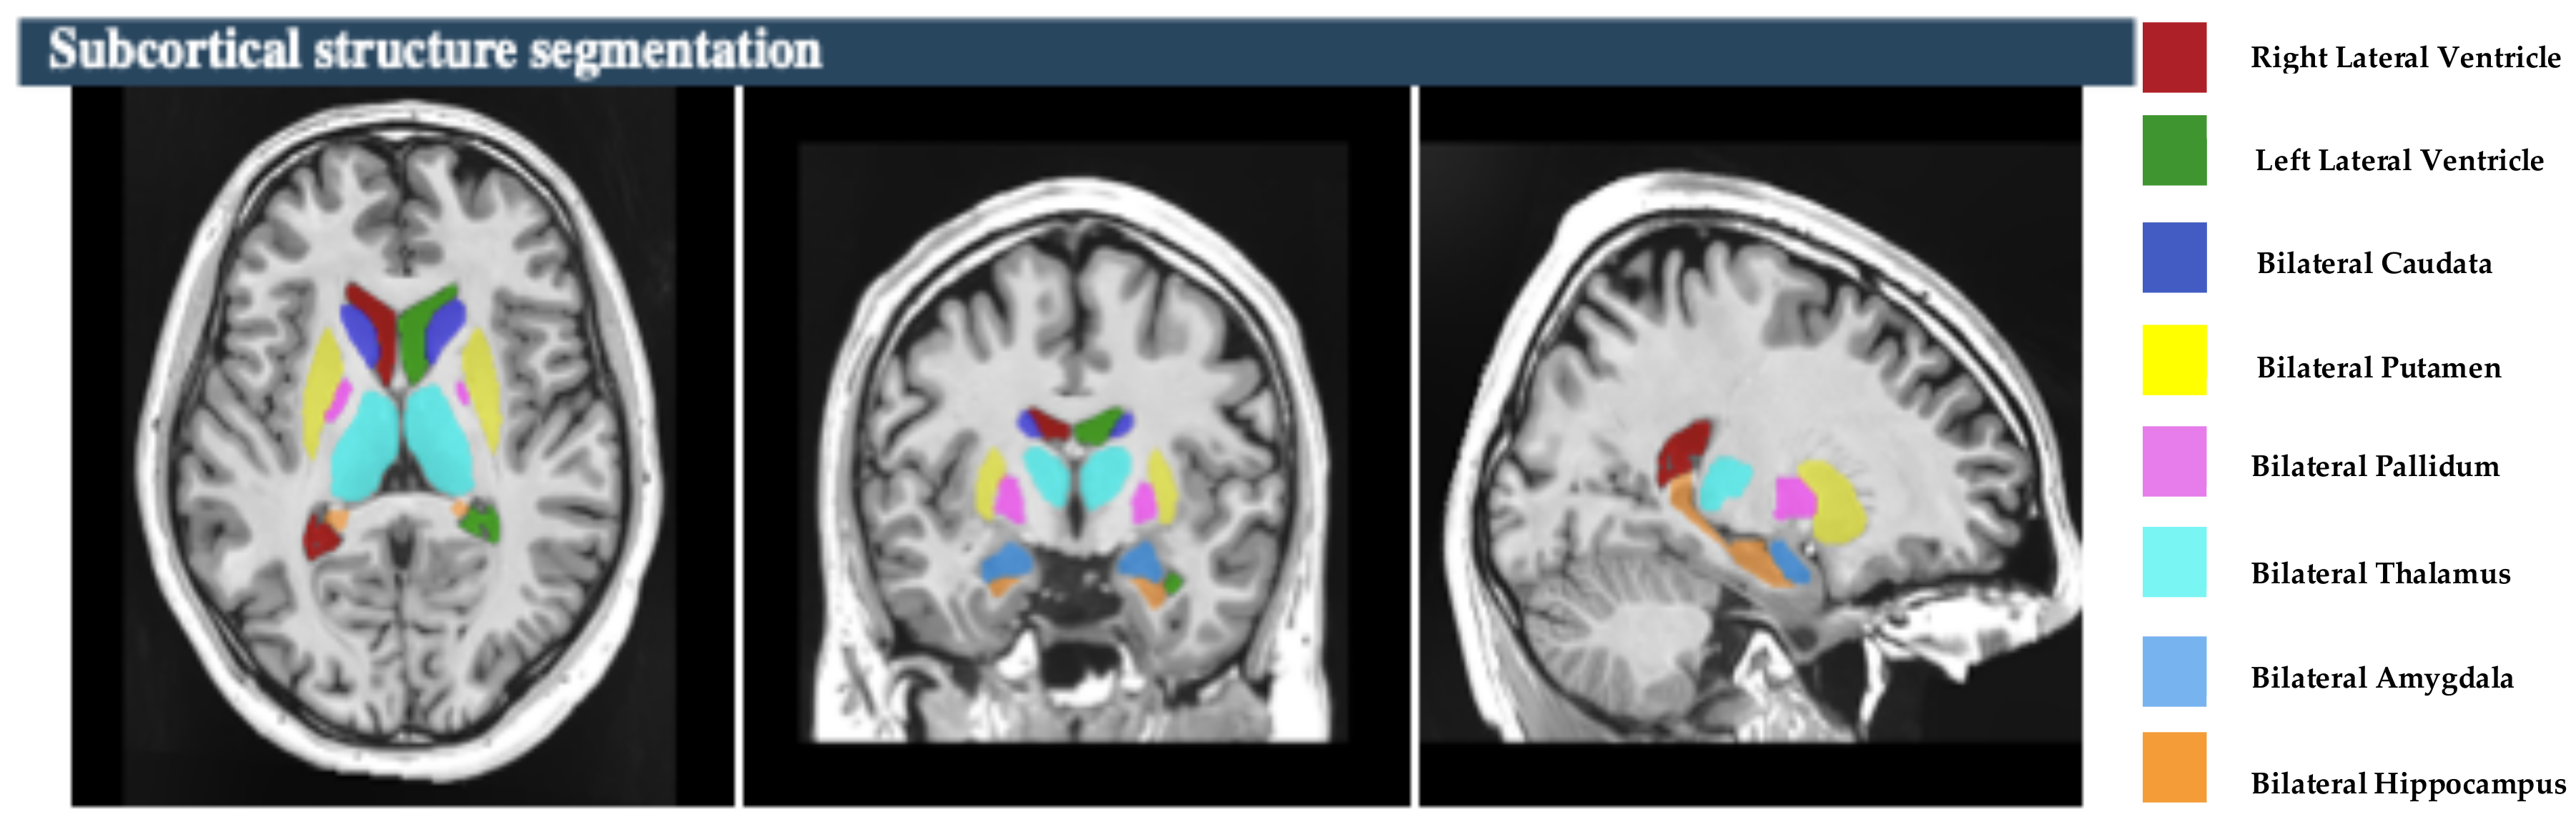

The raw data of MR brain images were analyzed using volBrain Online software that is an automated and online MRI brain volumetry system (https://volbrain.net/, accessed on 1 December 2024). AssemblyNet, VolBrain and HIPS-monospectral pipelines were used to assess brain tissue, subcortical structures and hippocampal subfields, respectively. The high resolution T1-weighted imaging volumes underwent standard pre-processing steps: denoising, coarse inhomogenity correction, MNI space registration, fine inhomogenity correction and intensity normalization. Then, the segmentation process was applied, which consists of the following steps: spatially adaptive non-local means denoising, rough inhomogeneity correction, affining registration to MNI space, fine SPM-based inhomogeneity correction, intensity normalization, non-local Intracranial Cavity Extraction (NICE), tissue classification, non-local hemisphere segmentation (NABS) and non-local subcortical structure segmentation, as depicted in Figure 1.

The study focused on eight subcortical structures, divided into right and left hemispheres: the putamen, caudate, pallidum, thalamus, hippocampus, amygdala, and nucleus accumbens, and lateral ventricles, as depicted in Figure 2. Also, this study focused on the five hippocampal subfields, divided into right and left hemispheres: cornu ammonis 1 (CA1), cornu ammonis 2 and 3 (CA2–CA3), cornu ammonis 4 and the granule cell layer of dentate gyrus (CA4-DG), the strata radiatum/lacunosum/moleculare (SR-SL-SM), and Subiculum, as depicted in Figure 3. The volumetric measurements of the global tissue estimation (GM, WM, and CSF), macrostructures (cerebrum, cerebellum, vermis, and brainstem), subcortical structures (putamen, caudate, pallidum, thalamus, hippocampus, amygdala, nucleus accumbens, and lateral ventricles), hippocampal subfields (cornu ammonis 1 (CA1), cornu ammonis 2 and 3 (CA2–CA3), cornu ammonis 4, and the granule cell layer of dentate gyrus (CA4-DG), strataum radiatum/lacunosum/moleculare (SR-SL-SM) and Subiculum) were extracted.

Figure 2. The process of subcortical structure segmentation. Right panel shows the color coded of hippocampal subfields that are overlaid onto the subject’s high-resolution T1-weighted anatomical scan [subject 10].